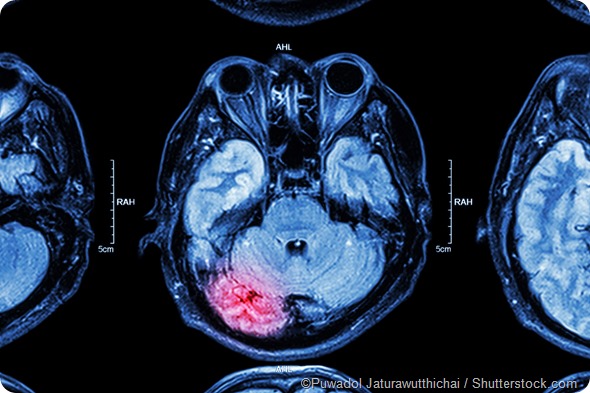

MRI brain injury